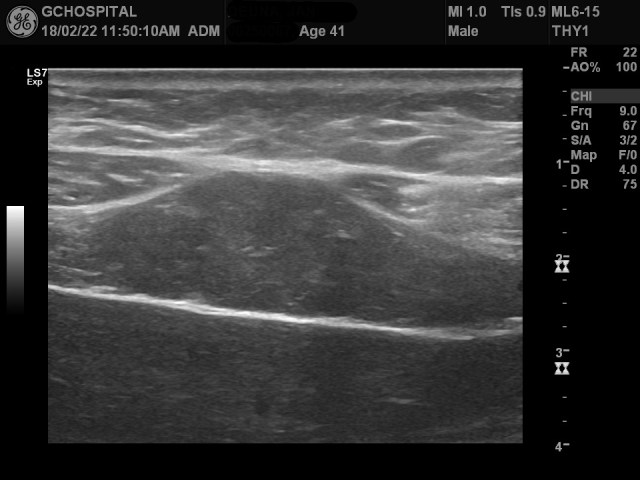

위는 12MHz frequency linear probe를 통해 간 좌엽을 스캔한 영상입니다. 일견 보기에는 간표면이 매끄럽고, 별다른 문제가 없어보입니다.

하지만, 이를 좀더 확대해보면, 간 피막의 윤곽이 울퉁불퉁하게 요철이 보이고, 왼쪽 영역에선 focal nodularity도 확인할 수 있습니다.

다른 부위에서 얻은 영상에서는 간 피막의 윤곽이 더 뚜렷하게 울퉁불퉁해보입니다.